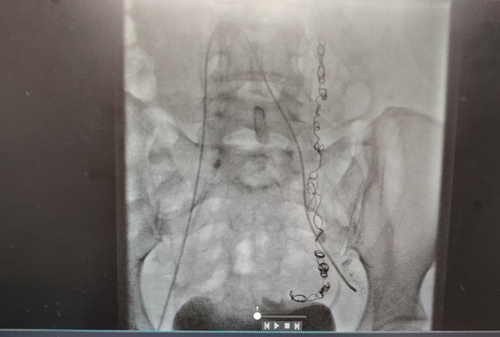

手術(shù)臺上,張濤教授化身“血管工程師”,在局麻下為小雪實(shí)施了“腔靜脈、盆腔靜脈造影 + 盆腔靜脈栓塞術(shù)”。

手術(shù)過程中,靜脈造影就像給血管來了一場 “高清直播”,清晰地展示出左側(cè)卵巢靜脈明顯迂曲增粗,造影劑滯留延遲,盆腔靜脈叢血流瘀滯,左側(cè)卵巢靜脈叢多處病灶更是呈現(xiàn)出團(tuán)狀迂曲增粗、側(cè)枝豐富的“亂象”。

發(fā)現(xiàn) “罪犯血管” 后,張濤教授憑借精準(zhǔn)定位,采用泡沫硬化劑聯(lián)合彈簧圈栓塞術(shù),直接阻斷其血供,徹底切斷“罪犯血管”的“通路”。